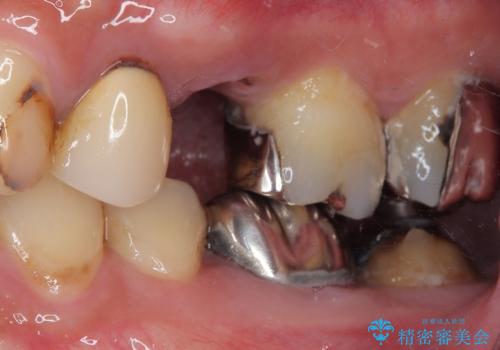

診査の結果、該当歯は**虫歯が歯肉の奥深くまで進行し、根だけが残っている状態**でした。

今回は、外科処置の回数を減らし、患者様の負担を最小限にするため、

**抜歯と同時にインプラントを埋入する「抜歯即時インプラント」**を選択しました。